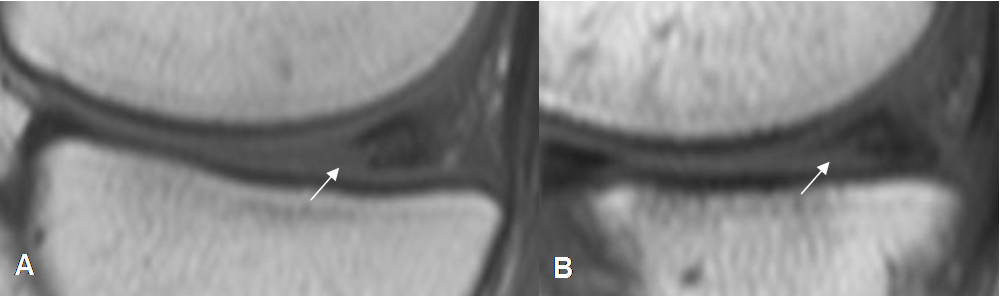

Fig 66. Lesión meniscal grado 1.

A y B: RM sagital en T1. Areas redondeadas en hiperintensas en T1, por degeneración mucoide.